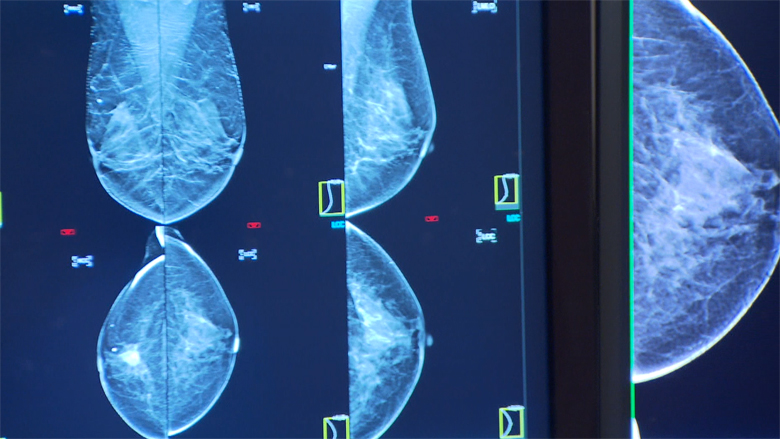

Uit onderzoek van het ziekenhuis Antoni van Leeuwenhoek blijkt dat vrouwen die eerder een ivf-behandeling hebben gehad, niet meer kans hebben op het ontwikkelen van borstkanker dan andere vrouwen. Ook niet na langere tijd (meer dan 20 jaar).

Door de grote hoeveelheid hormonen bij ivf zou de kans op borstkanker toenemen, zo dachten wetenschappers eerder. Uit de studie van het Antoni van Leeuwenhoek blijkt dat nu niet waar. Na zes behandelingen werd zelfs een lager risico gevonden, zo concluderen de onderzoekers.